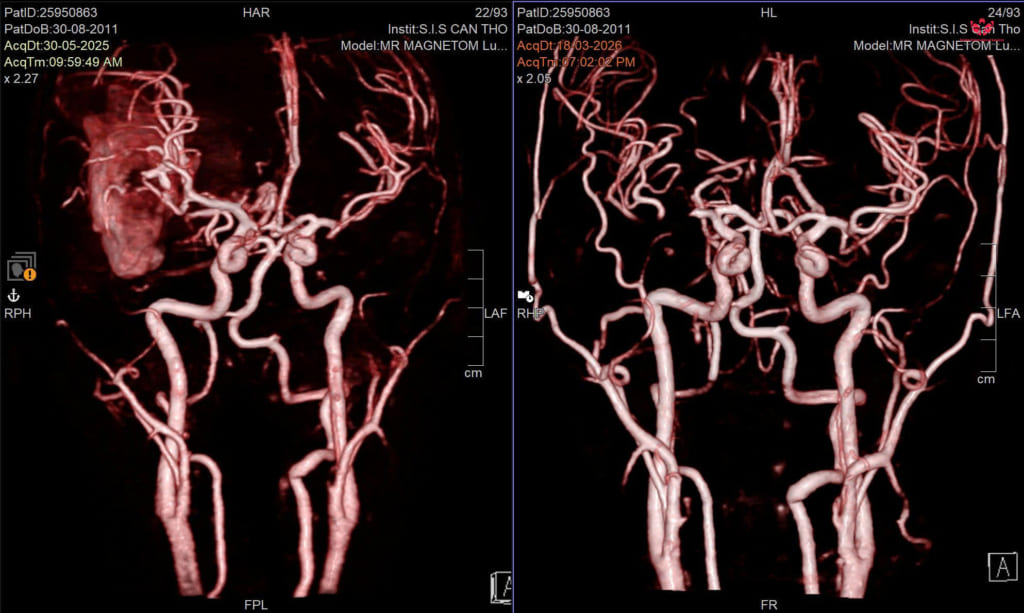

Hình ảnh chụp cộng hưởng từ MRI não của nam sinh Trước và Sau điều trị.

Tại Bệnh viện Đa khoa Quốc tế S.I.S Cần Thơ, các bác sĩ nhanh chóng xác định em bị xuất huyết não do vỡ dị dạng mạch máu não (AVM). Đây là bệnh lý dị dạng mạch máu bẩm sinh, thường không có biểu hiện đặc biệt, cho đến khi chúng dọa vỡ hoặc đã vỡ với những cơn đau đầu đột ngột dữ dội và có thể cướp đi tính mạng trong thời gian rất ngắn.

BS.CKI Nguyễn Quang Hưng – Trưởng Đơn vị Phẫu thuật Thần kinh, cho biết, trong trường hợp này, bệnh nhân có dị dạng mạch máu não khá phức tạp đã vỡ kèm theo khối máu tụ lớn, do đó các bác sĩ đã lựa chọn chiến lược điều trị phối hợp nhằm tối ưu hiệu quả.

“Ngay khi nhập viện, bệnh nhân được cấp cứu và đánh giá nhanh, sau đó tiến hành can thiệp nội mạch để giảm lưu lượng dòng chảy, hạn chế nguy cơ chảy máu. Tiếp theo, ê-kíp phẫu thuật thần kinh thực hiện bóc tách và loại bỏ toàn bộ khối dị dạng.” – BS.CKI Nguyễn Quang Hưng thông tin.